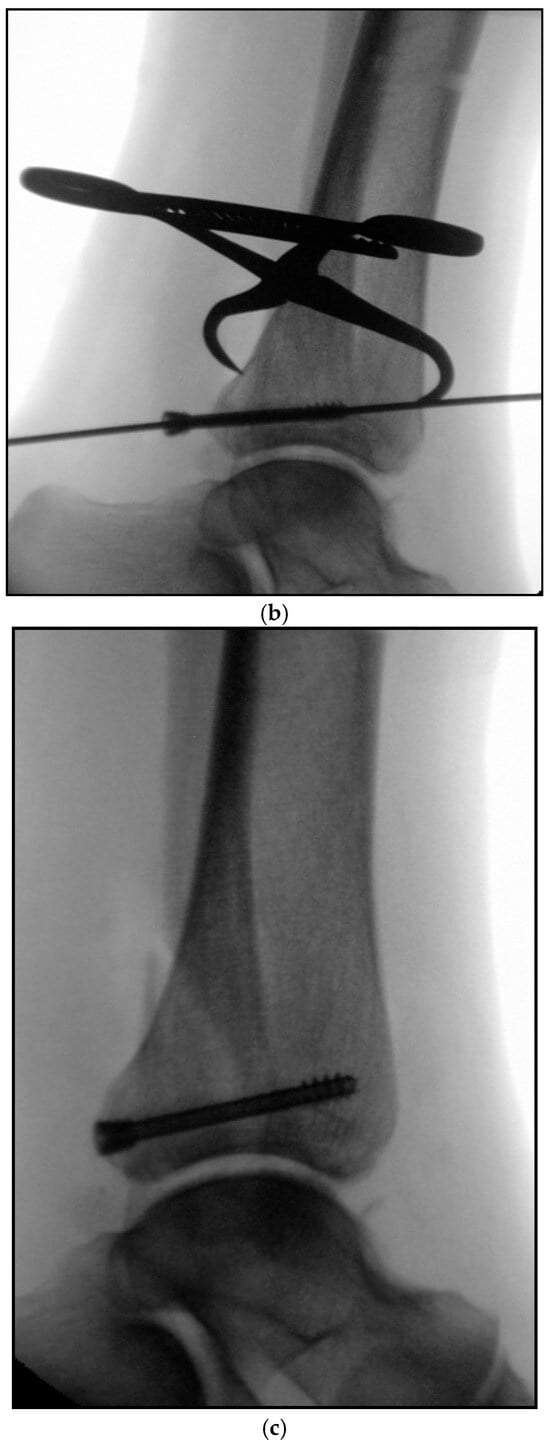

5.5. Reamed Intramedullary Locking Nail Fixation of the Distal Fibular Fracture